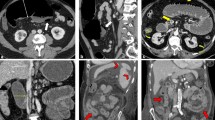

During the study period, 42 out of 126 hospitalized patients underwent contrast-enhanced WB-CTA, including 23 cases admitted to ICU. The main clinical indications in no-ICU patients included acute onset or unexplained worsening of dyspnea, sudden onset of edema of the limbs, and critical consciousness alterations. Worsening hypoxemia and D-dimer increase ( > 2-fold) were the main hallmarks in ICU cases. Overall, the mean time elapsed from fever onset and WB-CTA was 19.6 ± 6 days (including the pre-hospitalization period). Demographics and clinical features of the study population are reported in Table 1. As shown, there were no significant differences in gender or age between ICU and non-ICU patients, while active smokers’ frequency was higher in the former. Also, the prevalence of patients with comorbidities, like type II diabetes, was significantly higher among ICU cases, with most of them being also obese. The prevalence of systemic hypertension was similar in the two study groups, while no patients had an underlying chronic lung disease. SARS-CoV-2 related pneumonia was detected in all of them with an estimated mean CT disease extent of 13.7 according to the lung severity score by Zhao W et al [17]. Lung involvement was significantly greater in ICU patients, all of them requiring mechanical ventilation, as compared to non-ICU cases (16 ± 3.2 vs. 11 ± 4.1, p < 0.0001). Figure 1 shows representative bilateral pneumonia with ARDS-like features in an ICU patient. All patients were under anti-viral therapy with lopinavir/ritonavir and paracetamol as needed.

Axial thin-section baseline unenhanced lung CT scan in a 33-year-old patient who presented with fever and cough, ultimately requiring ICU admission due to significant worsening of respiratory failure. Diffuse bilateral confluent and patchy ground-glass and consolidative pulmonary opacities are evident from the lung apices (a, b) to the bases (c, d), with a total severity score of 20/24 (see text)